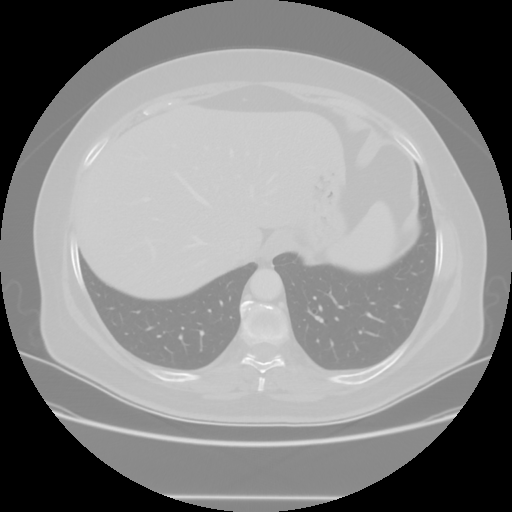

Original VENOUS CT scan

Lung window (WL -600, WW 1500 β†’ Low βˆ’1350, High +150)